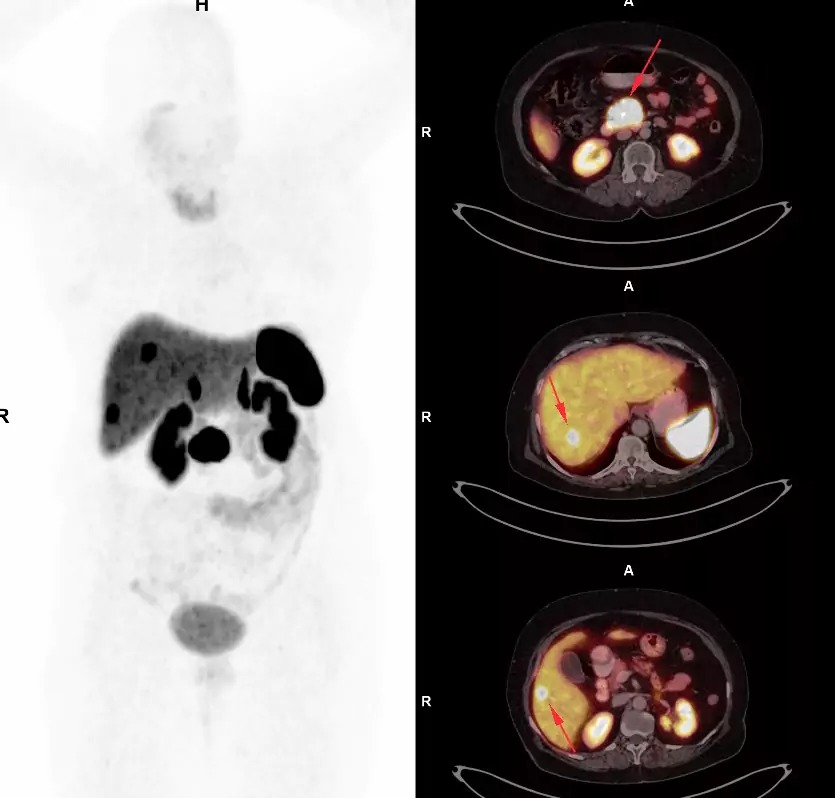

At Picture This, we offer clear and competitive DOTA scan price in Mumbai for advanced neuroendocrine tumor detection. Our state-of-the-art imaging technology delivers precise results, supporting accurate diagnosis and effective treatment planning. Each scan is conducted under the supervision of experienced radiologists, with a strong focus on patient comfort and safety. By combining affordability with cutting-edge imaging, we provide world-class diagnostic care across Mumbai. Monitor your health with accuracy and confidence—book your DOTA scan today and benefit from high-precision imaging at the best value in Mumbai with Picture This.